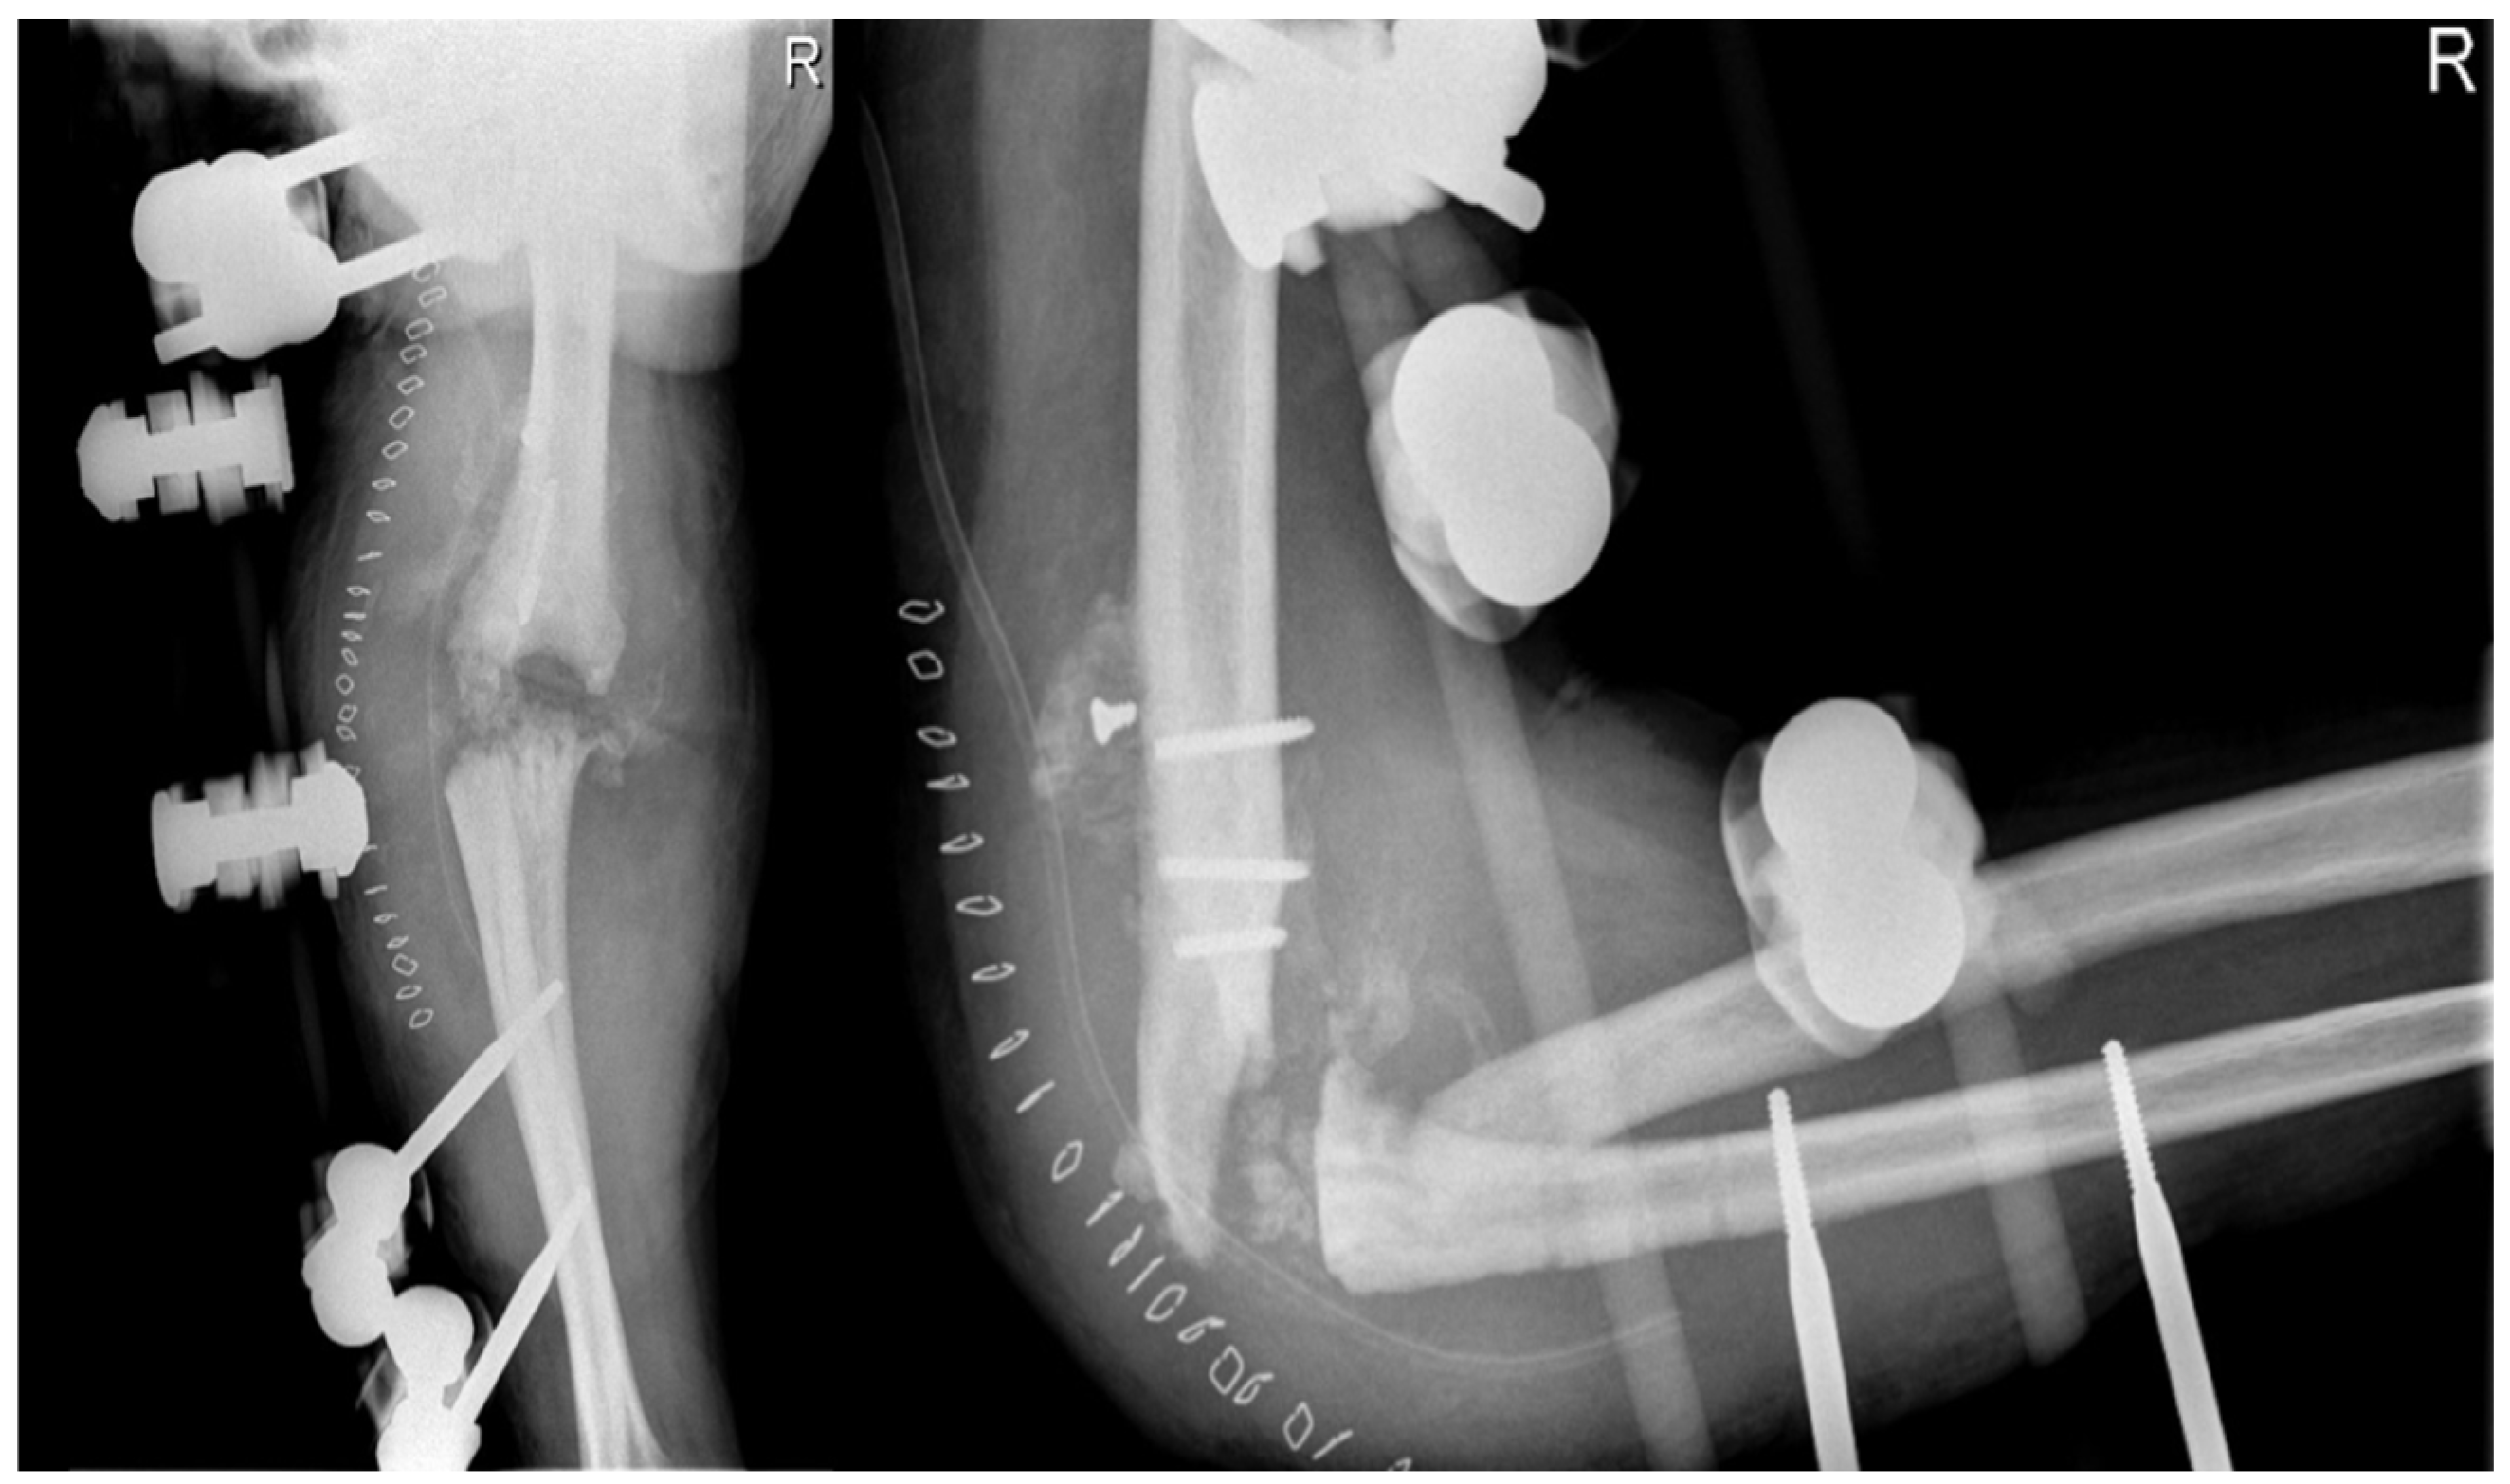

The patient’s clinical presentation necessitated a right elbow radiograph, which revealed substantial morphological changes in the joint’s bone structures, including osteolytic areas in the bone, as shown in Figure 2. The radiograph also displayed calcification of the periarticular soft tissue and radial head dislocation. Furthermore, the patient experienced an enlarging ulnar elbow mass, which was attributed to recurrent intra-articular bleeding affecting the periarticular soft tissue.

Figure 2.

X-ray anteroposterior and lateral views of the right elbow. First radiological presentation with subversion of the local anatomy of the bones and soft tissue around the elbow joint.

The patient also underwent magnetic resonance imaging (MRI) with and without contrast medium, which demonstrated subluxation between the articular surfaces of the elbow joint, edema and contrast enhancement in the spongy bone of the distal third of the humerus and proximal third of the radius, and a periosteal reaction at the humeral site without identifiable bone lesions, as shown in Figure 3. Additionally, the imaging revealed an abundant layer of joint effusion, with blood clots and loose bodies, at the joint level. The synovium appeared thickened and full of contrast enhancement, and the periarticular soft tissues also displayed thickening with edema and soft contrasting infiltration on the proximal ulnar side. In light of the known basic arthropathy and the patient’s clinical presentation, these radiological findings suggested an arthritic arthro-synovitis picture with soft tissue involvement, without excluding an infectious nature, rather than osteomyelitis, as there was no cavity of necrotic bone with fistula and bone marrow inflammation.

Figure 3.

Magnetic resonance imaging (MRI) coronal and sagittal T1 weight views of the right elbow. Involvement of periarticular soft tissue with a large mass through the articulation.